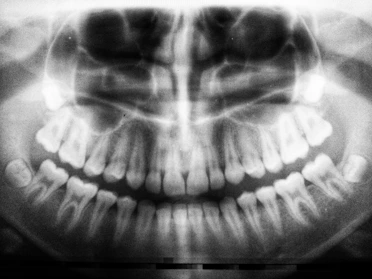

This is a one day course for a dental assistant who is already trained by a licensed dentist in taking x-rays. Enrollee must possess at least three months continuous on-the-job training in the State of Florida through assisting in the positioning and exposing of dental radiographic film. After performing skills in a clinical setting and passing a written exam with a grade of 75% or better a certificate will be issued.

To certify a dental assistant in the radiographic procedures listed below as prescribed by the Florida Board of Dentistry.

Radiographic Techniques